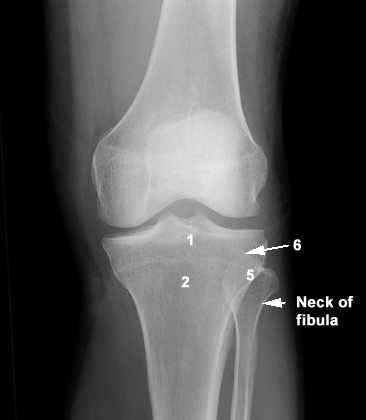

1: Head of Tibia  2: Tibial tuberosity  5: Head of Fibula  6: Styloid process of Fibula